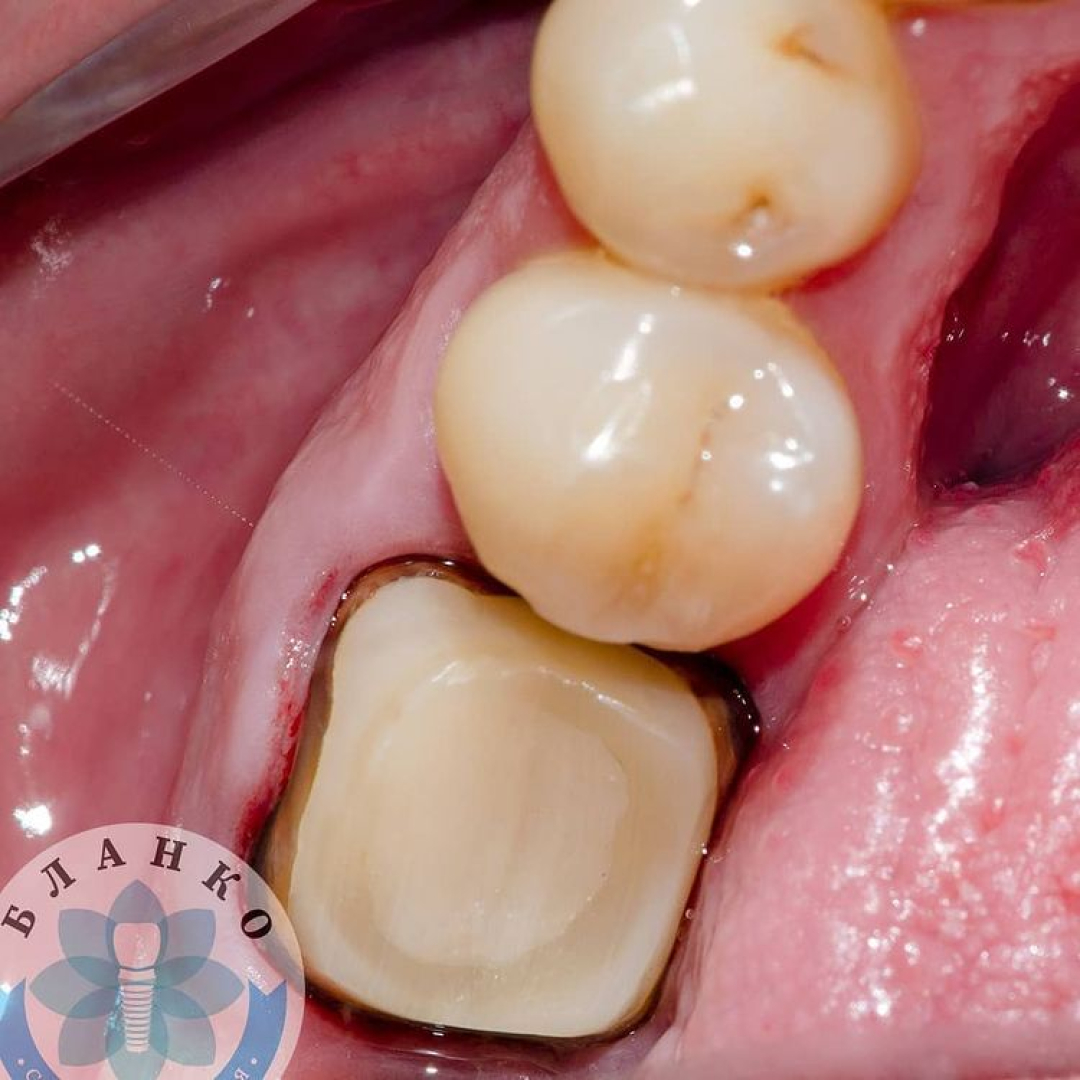

✳️Чтобы такой зуб вытащить с того света была проделана огромная работа, которая видна на всех последующих снимках, а именно:

— убрана несостоятельная реставрация

— извлечены анкерные штифты

— распломбированы и пролечены корневые каналы

— запломбированы корневые каналы

— твердые ткани зуба восстановлены с помощью специального материала